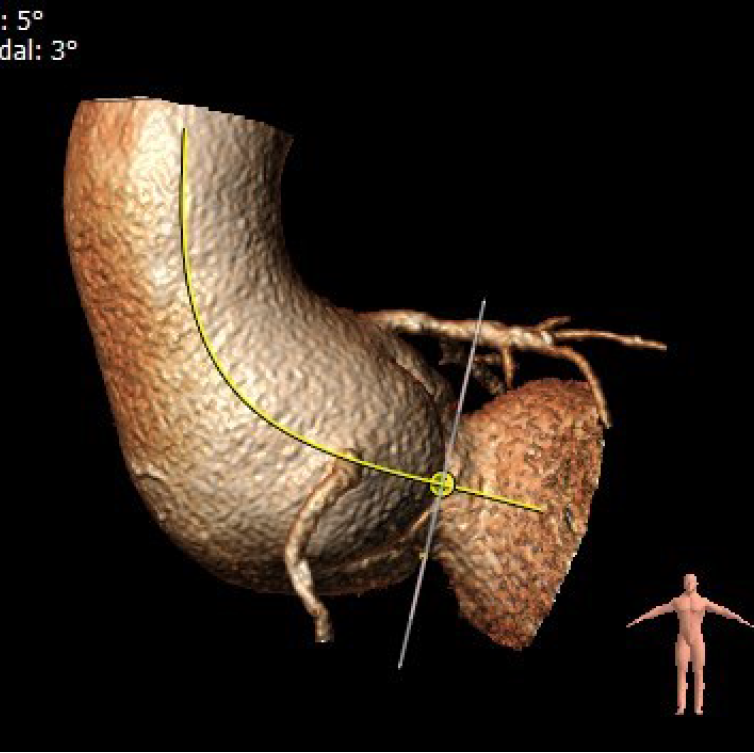

4.患者术中造影角度LAO:5°,CAU:3°。

最佳投照角度:LAO:5°,CAU:3°

主动脉根部角度:80°

升主动脉与主动脉窦部夹角:106°